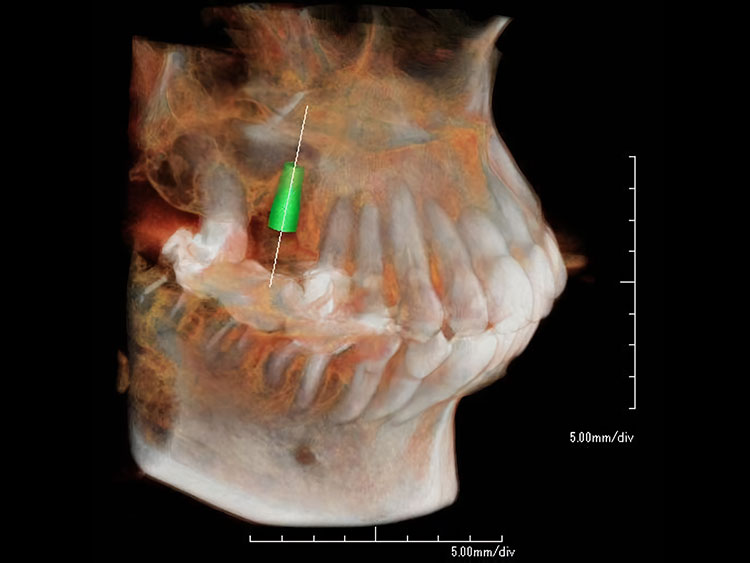

2.インプラントを埋め込む

CT事前にシュミレーション

シュミレーション通りにインプラント埋入

局部麻酔のもと、顎の骨にチタン製のインプラントを挿入します。 このインプラントが 新しい歯の土台となります。